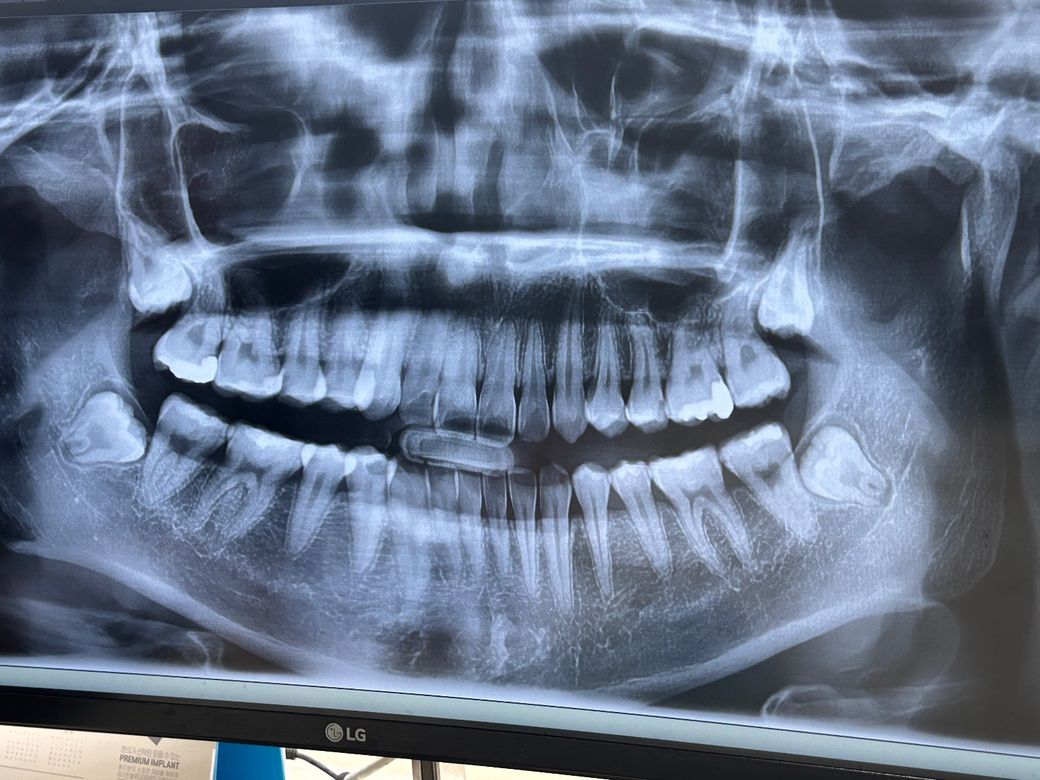

인접면 충치인가요? (엑스레이사진첨부)

오늘 치과가서 11개(어금니9개,앞니2개)진단받았습니다.... 하지만 원래가던 치과에서는 두개만 치료하라고했고, 잘 관리하면 멈출수도있다는 말을 들었어요.

하지만 11개 진단받은 치과에서는 이미 진행된 충치여서 관리를 열심히해도 절대 멈출수가없다고 합니다

혹시 인접면 충치인지, 잘 관리하면 멈출수있는지 확인해주실수있으신가요?

사진으로 봤을 경우에는 인접면에 조그만한 충치가 보이긴 하지만 심각하지는 않은 것으로 보입니다. 치실 등으로 치아 사이를 관리하면서 사용을 할 수 있을 것으로 생각됩니다.

위 엑스레이 사진은 정밀한 충치 진단에 큰 도움이 안됩니다. 대략적으로만 보고 충치 의심가는 부위는 정밀한 작은 엑스레이 사진 찍어봐야 합니다.

위 엑스레이 사진만 보고서 말씀드리자면 충치가 그렇게 많아보이진 않고 양쪽 위 두번째 작은 어금니 옆면은 충치가 있을 확률이 높습니다